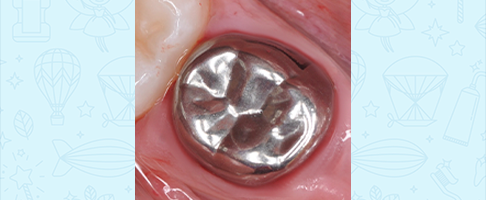

Лечение кариеса, восстановление зуба коронкой

Лечение пульпита молочного зуба, восстановление коронкой

Лечение пульпита молочного зуба, восстановление коронкой

Лечение пульпита молочного зуба, восстановление коронкой